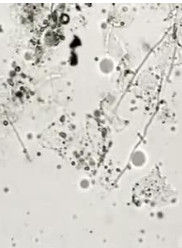

通過局部分泌物直接塗片檢查與培養明確診斷,鏡下容易看到黴菌的菌絲分枝和芽胞。白色念珠菌為卵圓形,革蘭氏染色陰性,但染色常不均勻,約3~5μm(較葡萄球菌大數倍),常產生長芽而不脫落(芽胞),以致假菌絲。診斷